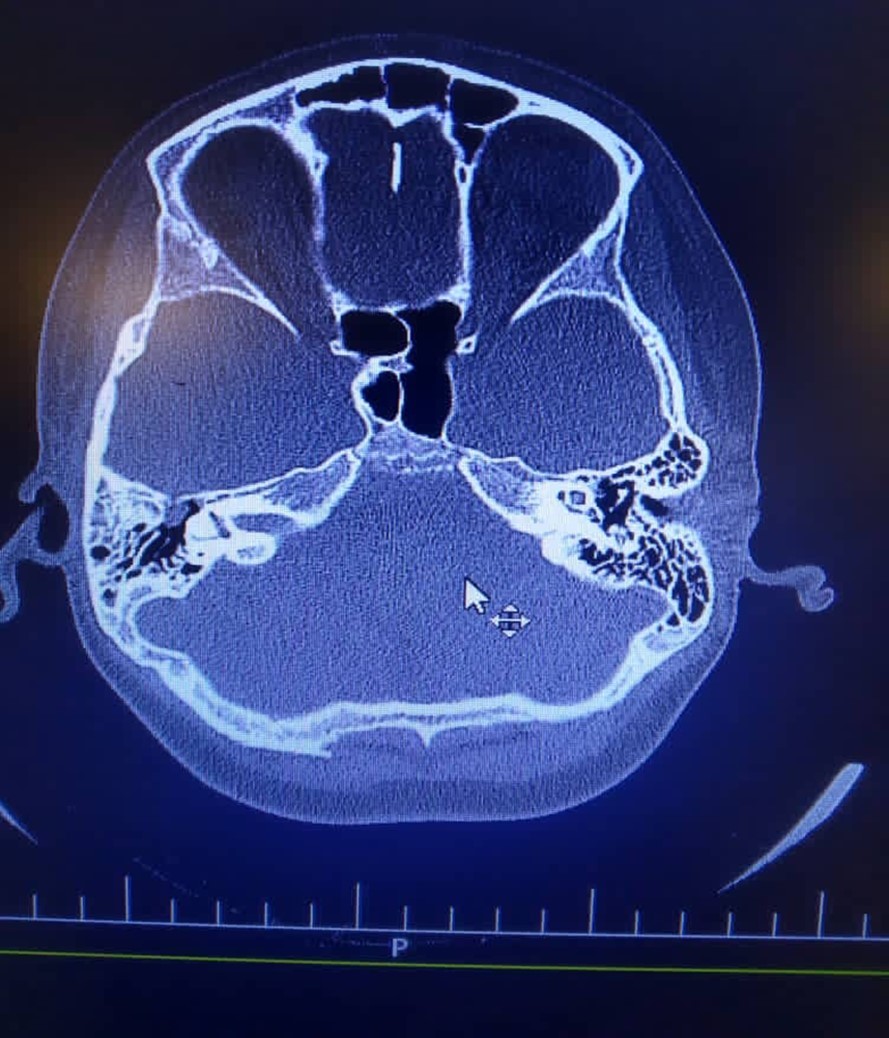

Temporal lobe meningoencephalocele is an uncommon anomaly in the face. As brain tissue herniate through the dural imperfection, cerebrospinal fluid (CSF) or a mass will appear in the mastoid, middle ear or the both. Here we present a 10 years old boy with right lobe temporal meningoencephalocele which results in CSF leakage and manifested with bacterial meningitis. He had a history of head trauma and bone fracture 3 years ago. In surgery the defect repaired and the patient showed improvement.